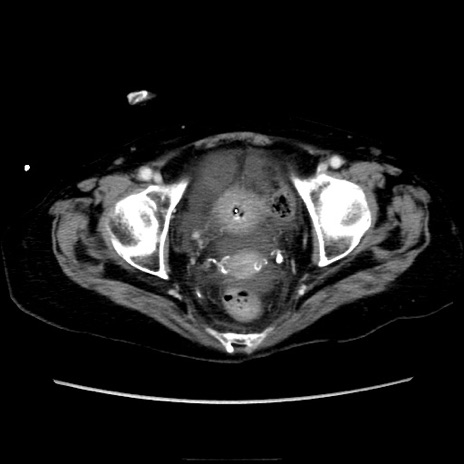

症例40(横断像)

【症例】90歳代女性

【主訴】腹痛・嘔吐

【現病歴】 食欲低下、嘔吐があり昨日他院受診。肺炎と診断され入院となる。入院後より腹部全体に圧痛あり。胃管留置され経過みていたが、症状持続するため、

当院転院となる。

【既往歴】胸椎圧迫骨折、胆石症

【身体所見】腹部:中央に激痛あり、圧痛あり、反跳痛不明

【データ】WBC 17100、CRP 18.82

横断像